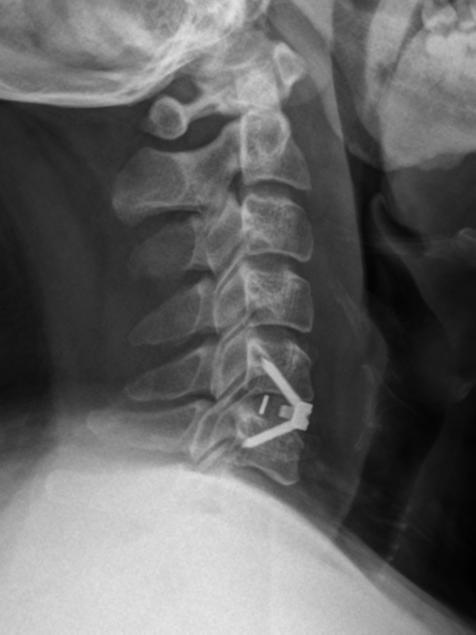

对于已确诊的脊髓型颈椎病患者,只要没有手术禁忌证,原则上应首选手术治疗。不过,对于受压较轻、病程较短、症状不重患者,也可以选择保守治疗,如卧床休息,减少颈椎负荷,佩戴颈托、颈围等支具等,但切记不要粗暴按摩。

六、颈椎手术安全吗?

对于颈椎手术,很多人会望而却步,误认为颈部大血管、神经太多,手术风险非常大,因此把病情一拖再拖。但事实上,无论是颈椎前路手术还是后路手术都是很成熟的手术,只要选择一个有经验的医生手术,风险都是可控的。

脊髓型颈椎病是一种发病隐匿、致残率高的颈椎病,需要引起我们足够重视。一旦确诊,原则上应该考虑尽早手术。不要耽误病情,错失手术良机。